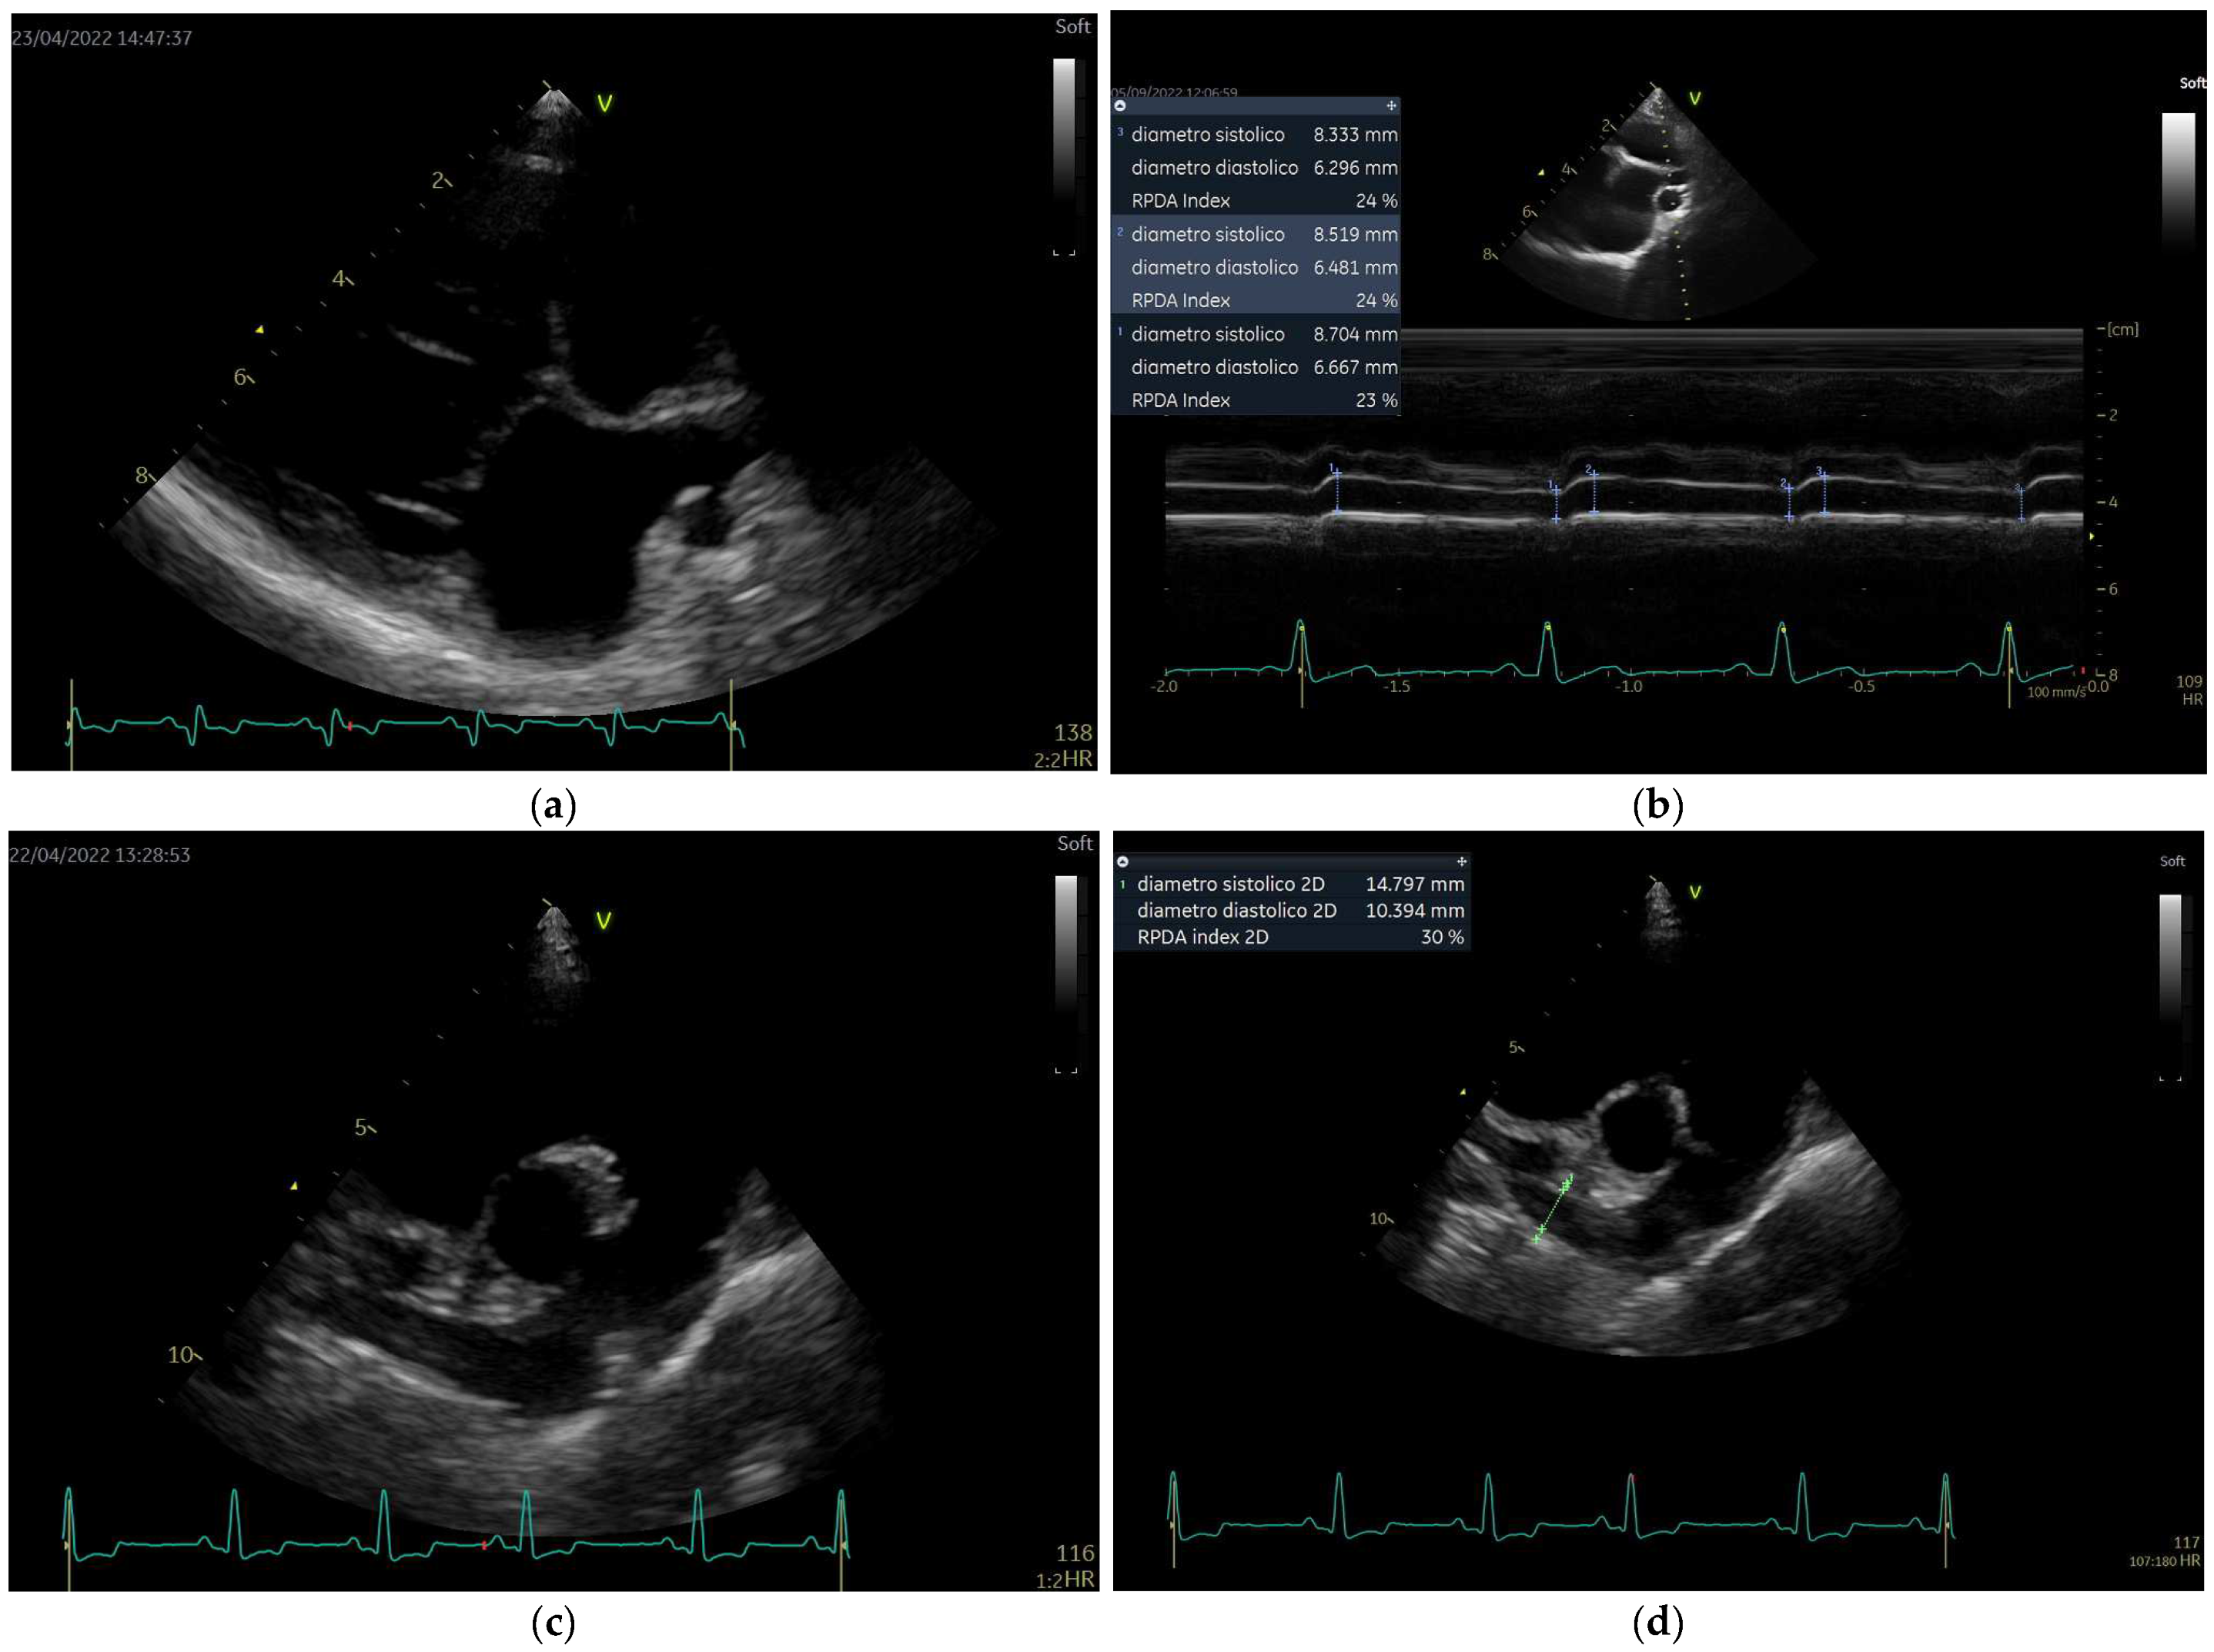

- method 2 (“Venco modified”): obtained in the same way as for method 1, but diameters of the RPA were measured with “the trailing edge to leading edge” (te-le) measurement convention (Figure 3).

- method 3 (“Visser classic”) [19]: obtained by B-mode study using View 2. Minimum diastolic and maximum systolic internal diameters were measured with “the trailing edge to leading edge” (te-le) method, using the same location of the RPA. The measurements were performed as perpendicular as possible to the internal borders, where RPA was clearly visible, starting from the frame with the largest diameter, and subsequently, scrolling frame-by-frame, the smallest diameter of RPA was measured, attempting to measure it at the same location.

- Method 4 (“Visser modified 1”, Visser “te-le”): using an M-mode image obtained from View 2, the diameters are measured using the “trailing edge to leading edge” (te-le) method.

- Method 5 (“Visser modified 2”, Visser “le-le”): using an M-mode image obtained from View 2, the diameters are measured using the “leading edge to leading edge” (le-le) method.